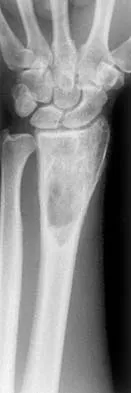

Figures 27a through 27c show the AP radiograph, MRI scan, and biopsy specimen of an otherwise healthy man who has a painful wrist. Serum chemistry studies are normal. What is the most likely diagnosis?